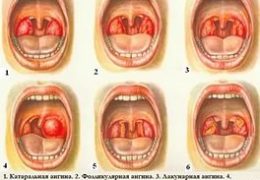

После этого начнется воспалительный процесс, и слизистая в полости рта покрывается сытью и через непродолжительное время появляются пузырьки (аналог герпеса на губах). Через несколько дней они самостоятельно начинают лопаться и превращаются в очень болезненные ранки. Из-за сильных болевых ощущений прием пищи сильно затруднен. Внешне ранки сильно напоминают гнойные язвочки.